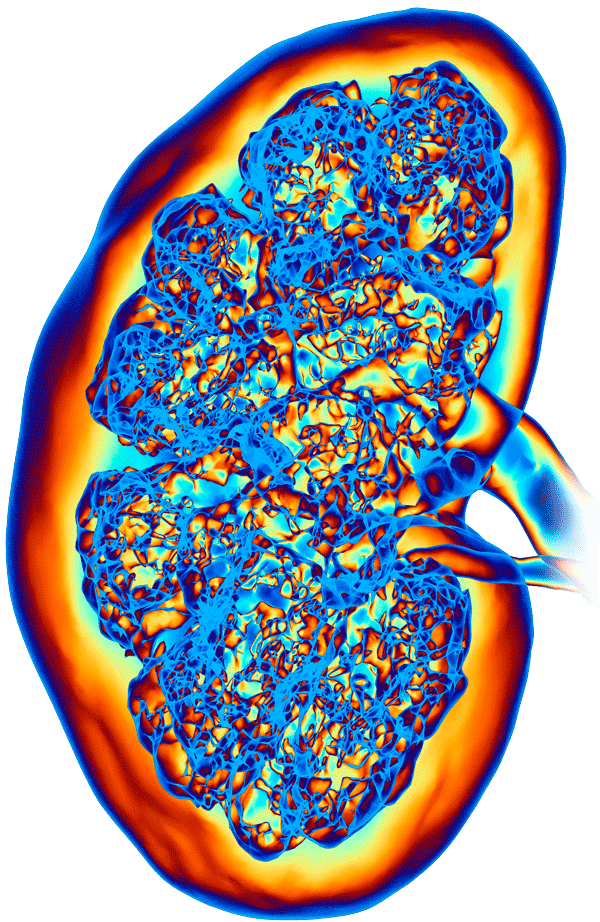

За счёт работы нашего отделения в системе городской больницы мы имеем полный спектр лабораторных и инструментальных исследований, что позволяет успешно лечить все типы урологических проблем.

Экстренная, плановая и консультативная помощь от квалифицированных врачей с многолетним опытом. Более 35 лет врачи урологического отделения больницы №15 используют эффективные методы диагностики урологических заболеваний и современный подход к лечению для того, чтобы вы вновь почувствовали себя здоровыми.

Специалисты нашего отделения нацелены на оказание вам своевременной, а главное, действенной помощи. Оперативное лечение осуществляется преимущественно малоинвазивным методом, что позволяет сократить риски негативного воздействия на организм и осложнений.

1. Новейшие современные методы диагностики и лечения с запатентованными авторскими методиками

5. Лечение всего спектра урологических

заболеваний